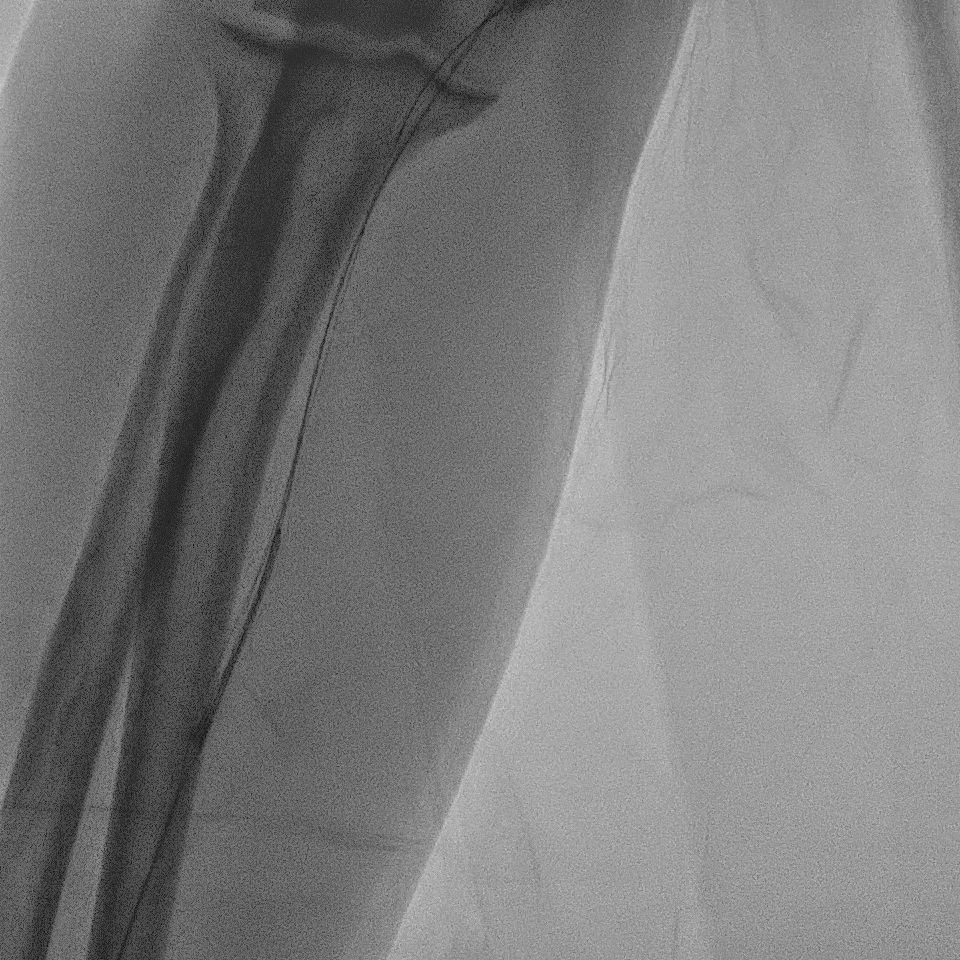

A right radial artery approach with 6Fr sheath was used. The right coronary system was engaged with 6Fr Judkin Right (JR4) guiding catheter. The posterior left ventricular branch was wired with Runthrough NS. Intravascular ultrasound (IVUS) showed distal RCA landing zone vessel size of 4.0-4.5mm in diameter. The mid RCA showed minimal luminal area (MLA) of 1.95mm2 with fibrous plaque and calcification at 12 o'clock. The proximal RCA landing vessel size was 4.5-5.0mm in diameter. The lesion was predilated with NC Trek Neo balloon 3.0x15mm. Attempted multiple times to deliver the stent SYNERGY 4.0X48mm but failed. The stent could not be passed into proximal RCA and eventually the distal stent edge crimpled and unable to be withdrawn into the guiding catheter. Tried to pull back system enbloc into the radial artery. Attempted to pull the stent into guider but failed again. The guiding catheter was removed. The stent was left with coronary wire in situ. Exchanged 6Fr radial sheath to slender sheath and attempted to snare stent with 2.0mm snare but failed. Attempted multiple wire wrapping technique with 3 BMW wires but failed. Decided to puncture right femoral artery with 8Fr sheath. A 7Fr JR4 guiding catheter was introduced into right brachial artery. A 7mm snare then snared the stent and removed it via femoral. The lesion was predilated with Scoreflex 3.5x20mm, stented with Supraflex Cruz 4.0x48mm and post-dilated with NC balloon 4.5mm. Result was TIMI 3 and no dissection.